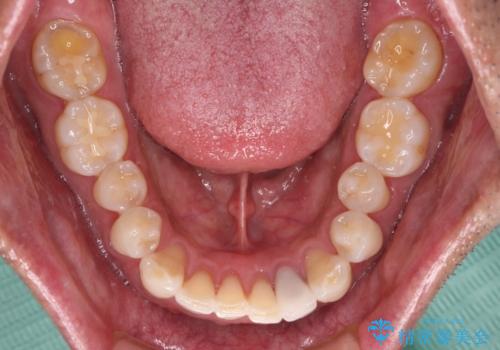

内側にある歯が干渉する 上顎前歯の部分矯正

- 上顎の前歯が内側にあり、下顎のセラミッククラウンと干渉することが気になるとのことで来院された患者様です。

上顎前歯にワイヤー装置を装着し、セラミッククラウンとは干渉しないようにしながら歯列を整えることとしました。

セラミッククラウンとの干渉はすぐに改善され、歯列も整いましたが、一方で、前歯で食事が噛みにくくなり、1年近い治療期間となりました。